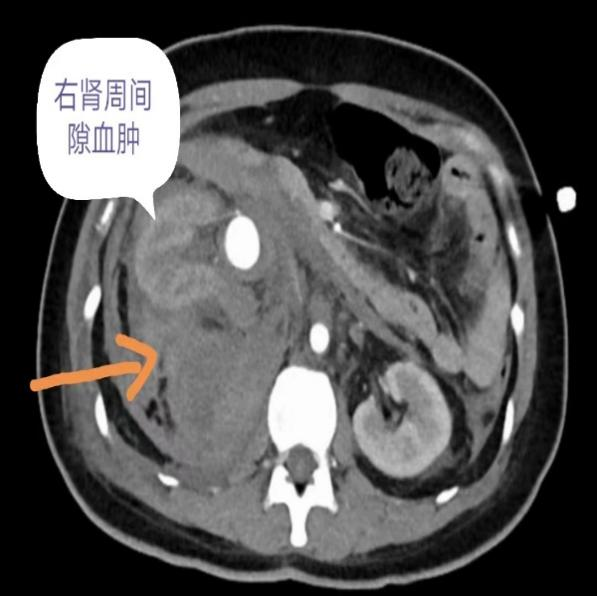

“当天晚上8点多,她转来时已面色惨白、右侧腰部剧烈疼痛,心率达到140次/分,存在失血性休克的可能。”据接诊的广医三院产科医生柯彩萍介绍,当时情况危急,产科与急诊科立即启动绿色通道,马上为丽丽输血输液,做腹部CT检查。结果让人心惊——医生发现丽丽右肾周间隙有大小约为11*8*5厘米的巨大血肿,盆腔、腹腔都有积液(图1)。腹部检查提示右肾动脉近肾门处有2厘米的动脉瘤破裂出血,而且右肾周间隙也有巨大血肿(图2)。

(图1)腹部CT提示丽丽右肾周间隙血肿,大小约11*8*5厘米